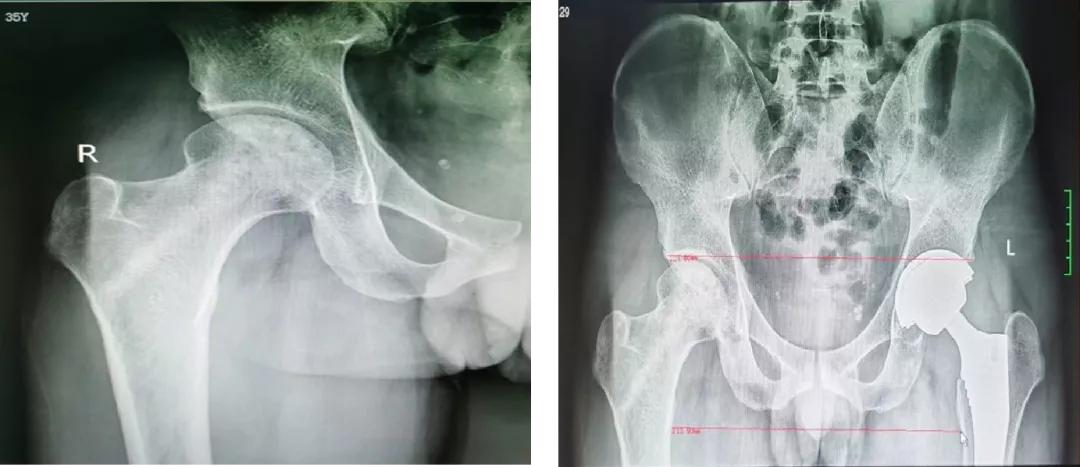

案例二

35岁的覃先生,也是双侧股骨头坏死,经同事介绍到关节与运动医学科住院,选择左侧人工全髋关节置换术、右侧机器人辅助下保髋治疗,术后效果良好,患者及其家属非常满意。

术前辅助检查

右侧保髋、左侧THA